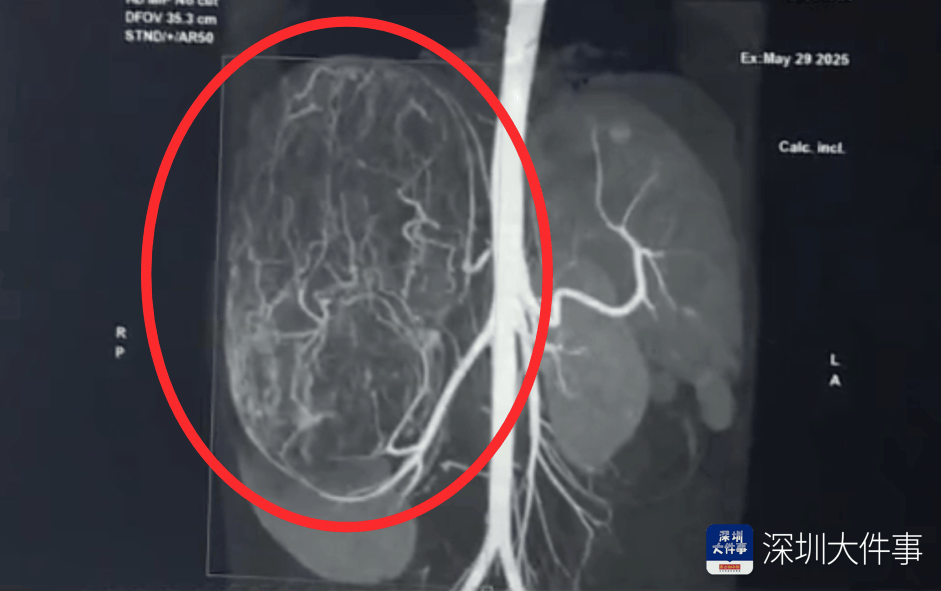

影像检查结果出来,所有人都倒吸一口冷气:一个直径27厘米(比篮球还大)的巨型肿瘤,霸占了整个腹腔右半边。肝脏被它硬生生挤到了肚脐眼以下的位置!

5月30日,医生为婷婷做手术,打开腹腔后,医生遇到了挑战:婷婷的肾动脉异于常人:正常人就1根肾动脉供血,她居然有3根。还有一支来自腹腔干动脉,一支来自腰动脉。

这三根“命脉”就盘踞在巨大的瘤体上,稍有不慎,剪错一根,就可能引发大出血。

手术团队屏气凝神,抽丝剥茧,一根一根精准找到、小心分离、稳稳阻断……经过3个多小时的精密操作:重达2.43公斤直径达27厘米的“巨无霸”肿瘤被完整端出。周围需要清扫的淋巴和脂肪组织也被清除。